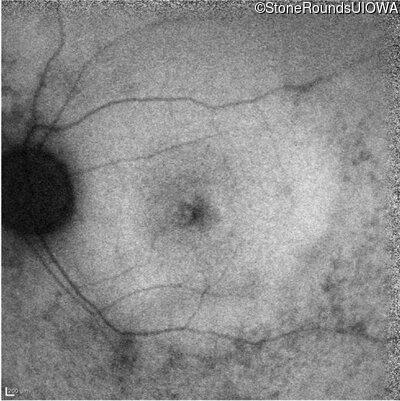

AR Retinitis Pigmentosa (IA1aiii)

Age at visit:

28 years

Diagnosis & molecular findings

Disease

Gene

Allele 1 variant(s)

Allele 2 variant(s)

Inheritance mode

AR Retinitis Pigmentosa

ZNF408

His455Tyr CAT>TAT

Arg567Stop CGA>TGA

AR